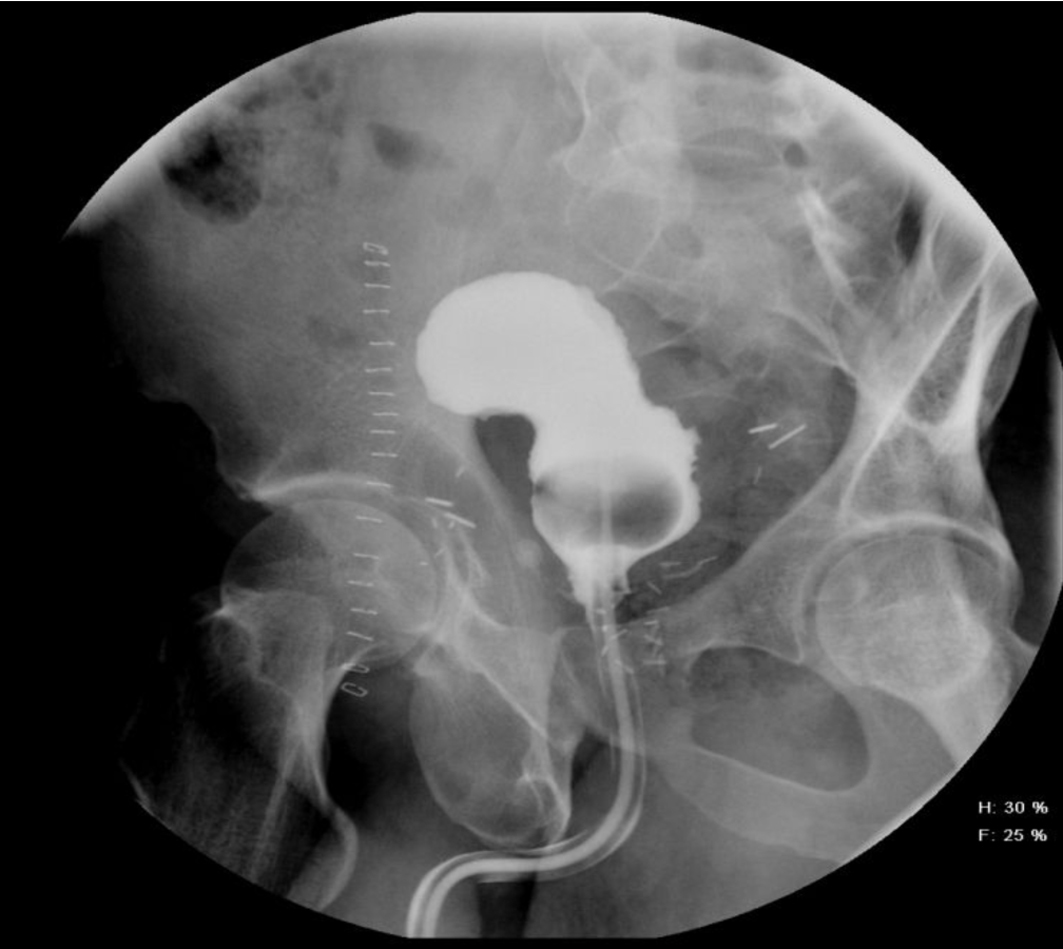

A 54-year-old African American male, presented to our facility with a prostate specific antigen (PSA) of 5.8 ng/mL. Prostate biopsy revealed three cores of Gleason 6 adenocarcinoma. On digital rectal examination he was found to have an approximately 60 g prostate, which was firm and smooth. He underwent an open retropubic radical prostatectomy (RRP). The pathologic specimen showed Gleason 7 adenocarcinoma occupying 20% of the specimen. The stage was T1cN0M0. On the fourth post-operative day, the patient presented to the Emergency Department in another facility complaining of chest pain and shortness of breath. A clinical diagnosis of pulmonary embolism (PE) was made and he was treated with a full dose of IV heparin. He subsequently developed hematuria and complained of lower abdominal pain. On physical exam, he was found to be pale, with diffuse abdominal tenderness, guarding and tachycardia. The patient was then transferred to the Surgical Intensive Care Unit (SICU) at our facility. He received two units of packed red cells. A cystogram showed complete disruption of the UVA with displacement of the bladder neck in the left upper quadrant of the abdomen producing a “pie in the sky” appearance. However, there was no evidence of urinary extravasation indicating an intact bladder neck (Fig. 1, 2). A CT scan revealed a very large pelvic hematoma displacing the bladder neck towards the left upper quadrant (Fig. 3). An IVC filter was inserted to prevent migration of thrombi so that he could discontinue the use of anticoagulants. Patient was managed conservatively for 6 - 8 weeks with gentle traction, and this helped maintaining the bladder neck within the pelvis. A cystogram showed no extravasation of urine. The Foley catheter was removed. The patient voided well initially; however, he developed bladder neck contracture (BNC) after 2 weeks. He was managed with dilation of the bladder neck, but the bladder neck did not return to the pelvis. It was found to be 2 cm away from the urethra, and a “pseudo-tunnel” made of scar tissue was seen between the true bladder neck and the membranous urethra. A surgical approach was used to explore the patient and the “pseudo-tunnel” was resected. Re-anastomosis of the bladder neck with the urethra was performed. The patient has remained continent since then and voids with minimal post void residual urine. There has been no recurrence of BNC (Fig. 4, 5). He needs intra-cavernous injections to help with erections. His post-operative PSA has remained undetectable.

![]() Click for large image | Figure 4. It shows post-operative pericatheter urethrogram with normal bladder neck and urethra. |

![]() Click for large image | Figure 5. Post-drainage film showing absence of extravasation. |